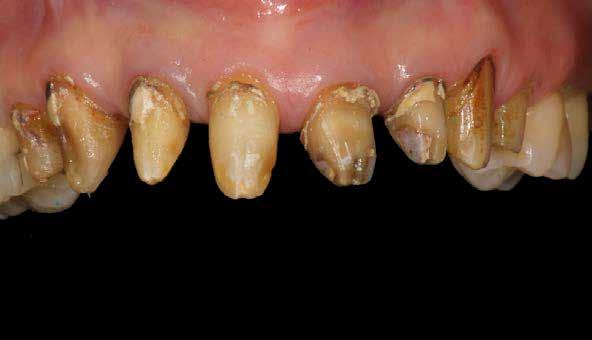

2015-ben egy 47 éves férfi páciens állkapocs-ízületi panaszai miatt kereste fel a rendelőnket. Ezen felül esztétikai problémát jelentett számára, hogy az egyik felső nagymetszőfogán lévő héj eltört (1-3. ábrák). A klinikai és radiológiai vizsgálatot követően megállapítható volt, hogy a páciens kifejezett bruxizmusa miatt csökkent a harapási magassága, és jelentős mennyiségű saját foganyagot abradált el (4. ábra)

1. ábra: A beteg esztétikai problémájára kért megoldást a régi restaurációk természetellenes megjelenése, továbbá a múltban lezajlott periodontitis következtében kialakult fekete háromszögek miatt. A szövetek visszahúzódása következtében a fogpótlás széle jól láthatóvá vált, a papilla csúcsok elvesztése és a koronák közötti számos fekete térrel együtt, komplex terápiás ellátást igényelt.

2. ábra: A parodontális problémák nem sebészeti kezelési terve a következőkből állt: fogkő-eltávolítás és gyökérsimítás, a korábbi rögzített fogpótlás cseréje, a marginális szövetek helyreállítása, és egy új, esztétikailag kedvezőbb gingivális szerkezet helyreállításának megkönnyítése.